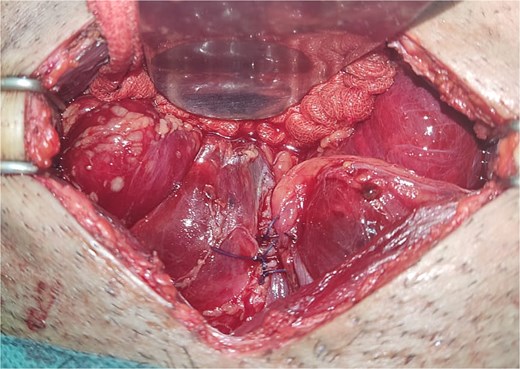

All seven cases of bladder rupture both spontaneous and traumatic were treated surgically via exploratory laparotomy to repair the injury (see Fig. 2). In both types of cases, the ruptured bladder was successfully closed (see Fig. 3). Postoperatively, Redon drain was removed on the second day, and a urinary catheter was maintained for 3 weeks to aid healing.

The image shows an extraperitoneal bladder rupture, revealing a tear in the bladder wall and damage to surrounding tissues.